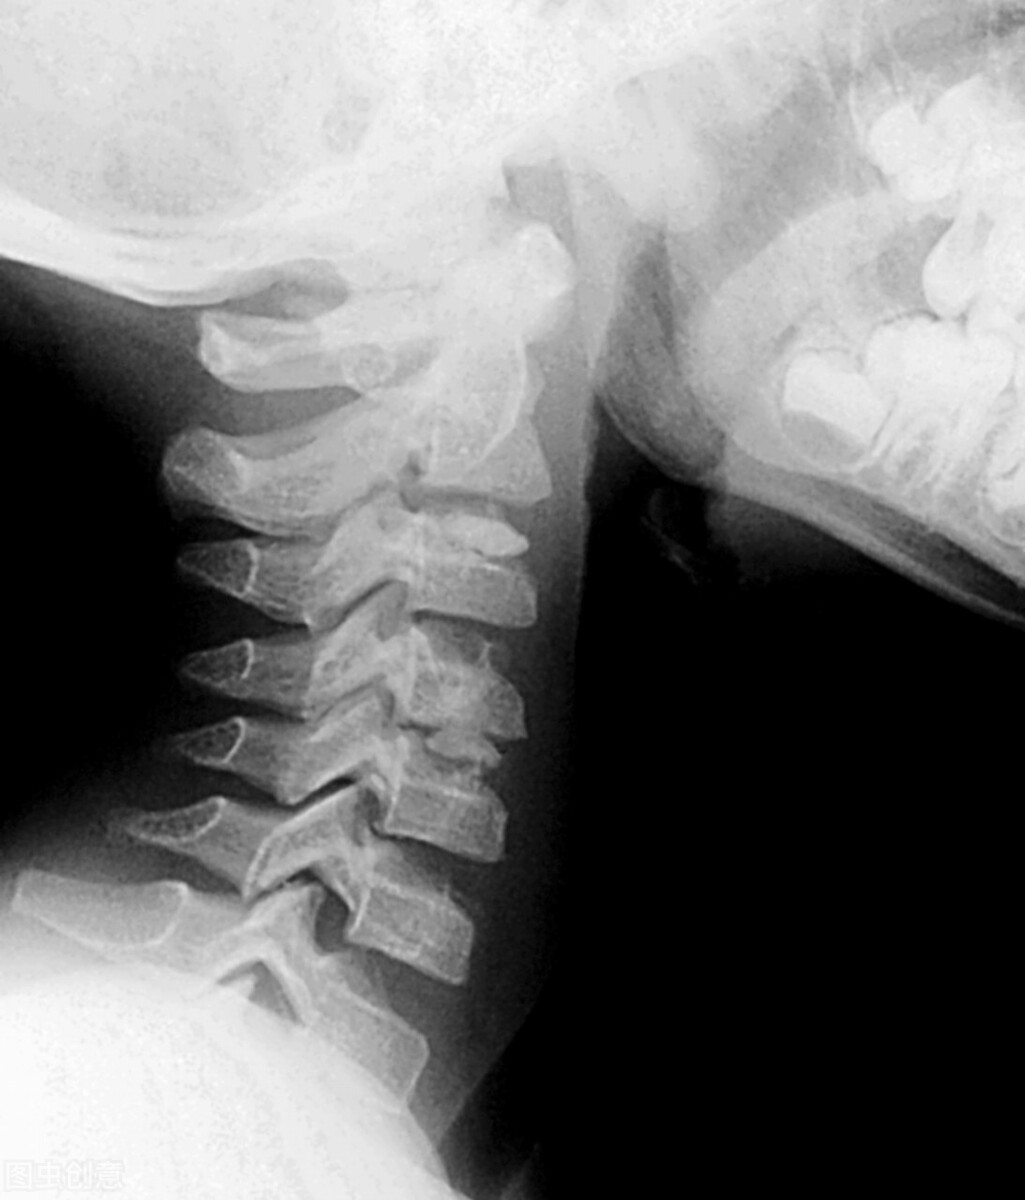

三、颈、胸、腰椎骨折史:

仔细询问受检者是否有颈、胸、腰椎骨折史;

让受检者取站立位,脱去外衣,检查受检者脊柱生理弯曲是否正常,是否存在后凸成角畸形;让受检者做前屈、后伸、侧弯、旋转等活动,观察脊柱活动是否正常;

让受检者取端坐位,身体稍向前倾,检查者以右手拇指从枕骨粗隆自上而下逐个按压各椎体棘突,或以叩诊锤叩击各椎体棘突,如受检者脊柱形态异常,活动受限或存在压痛、叩击痛等情况时,应进一步行脊柱x线检查以排除脊柱疾病,必要时或条件允许时可行腰椎CT检查和腰椎磁共振检查。